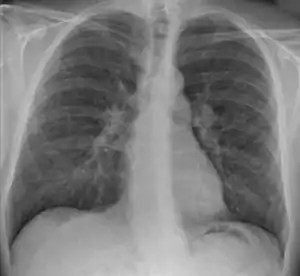

![]() | |

| Chest X-ray showing the typical nodularity of sarcoidosis, predominantly in the bases of the lungs. | |